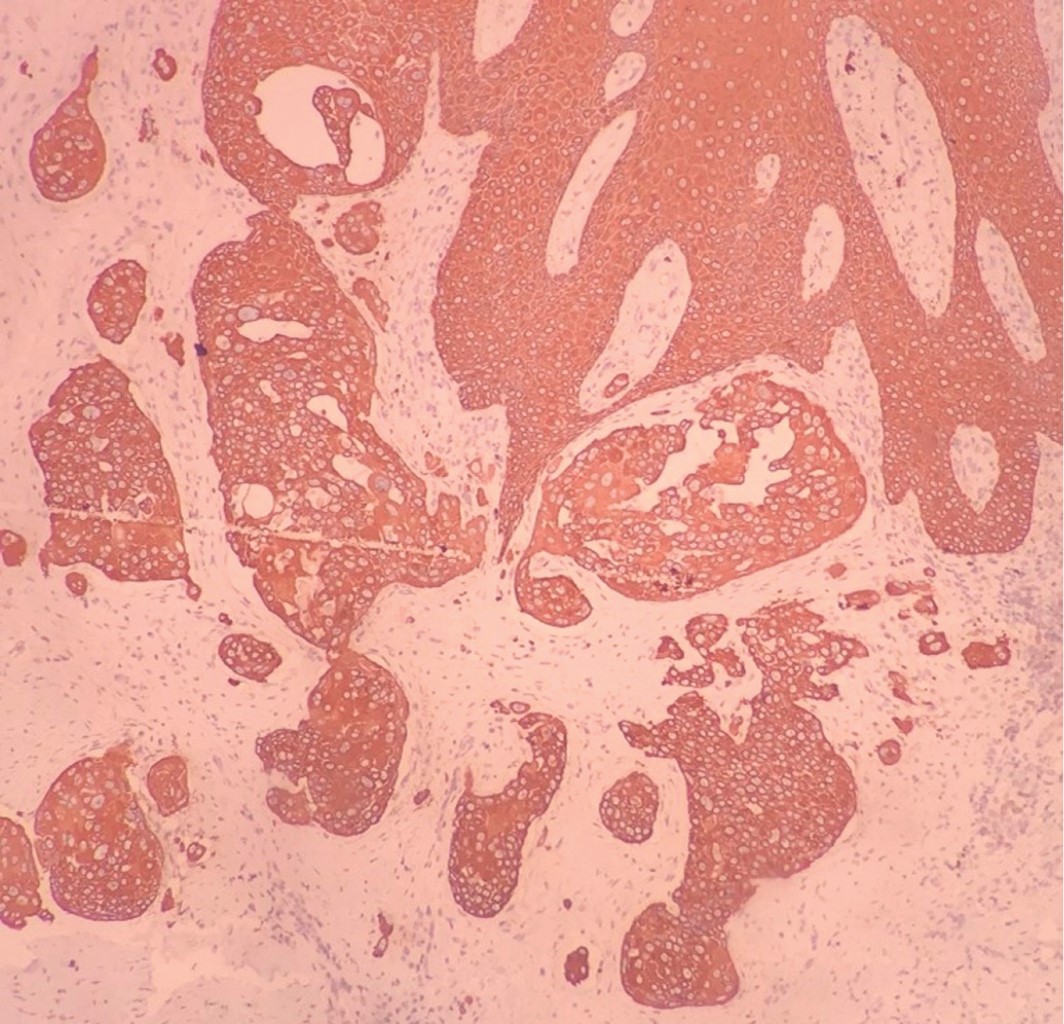

Hombre de 84 años con diagnóstico de metástasis de carcinoma epidermoide de origen primario desconocido en región inguinal izquierda, de dos años de evolución, en tratamiento paliativo con metotrexato y pregabalina durante un año, quien acude por presentar dermatosis diseminada a región inguinal izquierda y muslo izquierdo, constituida por incontables neoformaciones de diversos tamaños y formas del color de la piel, algunas amarillentas, de aspecto papular y nodular, de bordes bien definidos y en su mayoría, confluentes. En el resto de la piel se observa eritema, edema +++ y una úlcera en región inguinal. De evolución crónica y dolorosa (Figura 8). La tomografía axial computarizada (TAC) muestra adenopatías en región inguinal, bilaterales, de predominio en el lado izquierdo, y a nivel de la cadena iliaca externa derecha. Estudios de laboratorio: GGT 24 U/L, DHL 135 U/L, TGP 17 U/L, BT 0.22 mg/dL, BD 0 mg/dL, albúmina 3.3 g/dL, globulina 3.8 g/dL, Hb 12.6 g/dL, Hto 38.3%, Plt 421 × 103/µL, monocitos 16.6%, glucosa 92 mg/dL, CS 0.88 mg/dL. Debido a la rápida progresión, se inicia tratamiento con capecitabina y radioterapia (46 Gy/23 fracciones). Al notar incremento en la ulceración se suspende la quimioterapia por dos semanas para disminuir la toxicidad. Al término de la misma, se observa persistencia del edema e incremento de las lesiones. Se realiza biopsia incisional, cuyo estudio por inmunohistoquímica reporta CK7+, EMA+, P63+, CK20-, con lo cual se realiza el diagnóstico de carcinoma dependiente del folículo piloso compatible con carcinoma sebáceo (Figuras 9, 10, 11 y 12).

El estudio histopatológico es indispensable para su diagnóstico, ya que las formas tempranas pueden semejar benignidad. Este estudio muestra una colección de células sebáceas indiferenciadas, no encapsuladas, lobulares, de base dérmica, que pueden contener gotas de lípidos en su citoplasma, que son responsables del característico aspecto "espumoso" (con disposición central en los lóbulos). Los patrones histológicos pueden ser lobular, (similar a un comedocarcinoma), papilar y mixto; también se clasifican de acuerdo al grado de diferenciación como: bien diferenciados, moderadamente diferenciados o poco diferenciados. Se relacionan con mayor mortalidad los tumores poco diferenciados, la diseminación pagetoide (la más característica), el origen multicéntrico, el tamaño tumoral > 10 mm e invasión a estructuras vasculares, linfáticas y perineurales. Las tinciones por inmunohistoquímica para antígeno de membrana epitelial (EMA) (ausente en el carcinoma de células escamosas y basocelular) y adipofilina (97.1% de sensibilidad y especificidad) son las mejores pruebas complementarias para corroborar la diferenciación sebácea. Éstas permiten confirmar la existencia de citoplasma vacuolado; CD15+ y CD10- en los centros de los nidos tumorales; células tumorales negativas para el antígeno carcinoembrionario (CEA), la proteína S100 o la proteína del fluido de la enfermedad quística macroscópica (GCDFP). En comparación con sus contrapartes benignas, el carcinoma sebáceo expresa incremento de p53 y Ki-67 (marcadores de proliferación) y disminución de bcl-2 y p21 (marcadores antiapoptóticos).2,19,21-23

En casos de difícil diagnóstico, la inmunohistoquímica permite la diferenciación entre carcinoma sebáceo y carcinoma basocelular con diferenciación sebácea. Los sebaceomas con frecuencia presentan positividad para CK7, la inmunoperoxidasa para EMA y la adipofilina son positivas en adipocitos maduros. El estudio inmunohistoquímico negativo para BerEP4 permite diferenciarlo de un carcinoma basocelular con diferenciación sebácea. También se utiliza la determinación de receptores androgénicos, los cuales suelen mostrar positividad en estas neoplasias.2,5